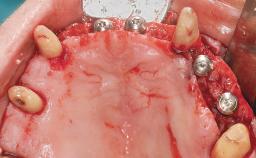

Immediate Loading of Eight Implants in the Maxilla and Six Implants in the Mandible and Final Restoration with Three-Unit and Four-Unit FDPs

Extensive scientific evidence has confirmed that immediately loaded implants with fixed full-arch provisional restorations can osseointegrate with success rates similar to conventionally or delayed loaded implants. A number of immediate-provisionalization techniques for edentulous jaws have been described. Some protocols differ when it comes to prefabricated provisional templates versus complete denture conversion; intrasurgical impressions versus direct relining; and cemented versus screw-retained provisional restorations. In this context, complete-denture conversion has been proposed for either intrasurgical impressions or direct relining. Another possibility is the utilization of a prefabricated provisional to be adapted either in the mouth (by direct relining) or in the laboratory (on a working model obtained from an intrasurgical impression).

# of Implants 14

Type of Implants One-Piece

Defining Characteristics Fully edentulous upper jaw to be rehabilitated with four or more implants

Modality 6+ implants with immediate loading

Bone Volume Horizontally and vertically sufficient